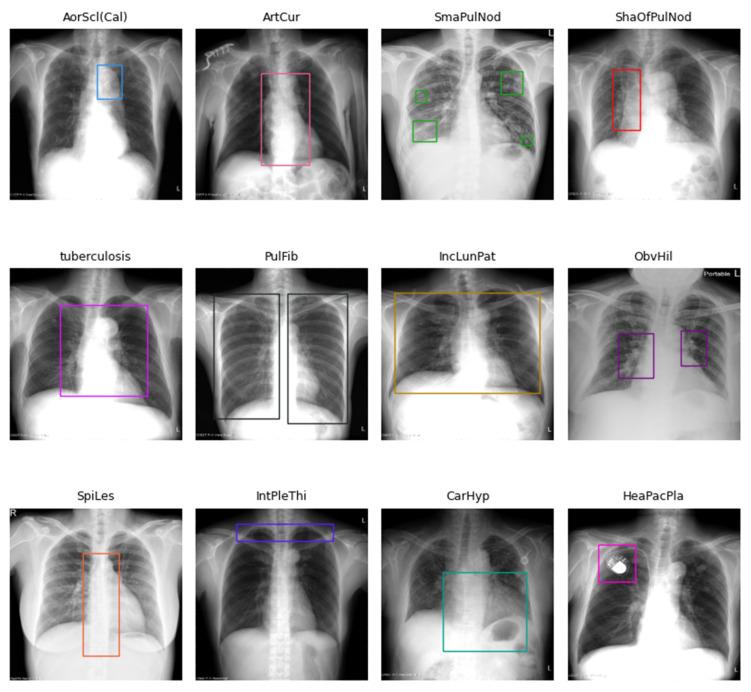

基于深度学习的胸部X光图像疾病检测与定位目标检测策略

Deep Learning-Based Object Detection Strategies for Disease Detection and Localization in Chest X-Ray Images.

Chest X-ray (CXR) images are commonly used to diagnose respiratory and cardiovascular diseases. However, traditional manual interpretation is often subjective, time-consuming, and prone to errors, leading to inconsistent detection accuracy and poor generalization. In this paper, we present deep learning-based object detection methods for automatically identifying and annotating abnormal regions in CXR images.

METHODS

We developed and tested our models using disease-labeled CXR images and location-bounding boxes from E-Da Hospital. Given the prevalence of normal images over diseased ones in clinical settings, we created various training datasets and approaches to assess how different proportions of background images impact model performance. To address the issue of limited examples for certain diseases, we also investigated few-shot object detection techniques. We compared convolutional neural networks (CNNs) and Transformer-based models to determine the most effective architecture for medical image analysis.

RESULTS

The findings show that background image proportions greatly influenced model inference. Moreover, schemes incorporating binary classification consistently improved performance, and CNN-based models outperformed Transformer-based models across all scenarios.

CONCLUSIONS

We have developed a more efficient and reliable system for the automated detection of disease labels and location bounding boxes in CXR images.